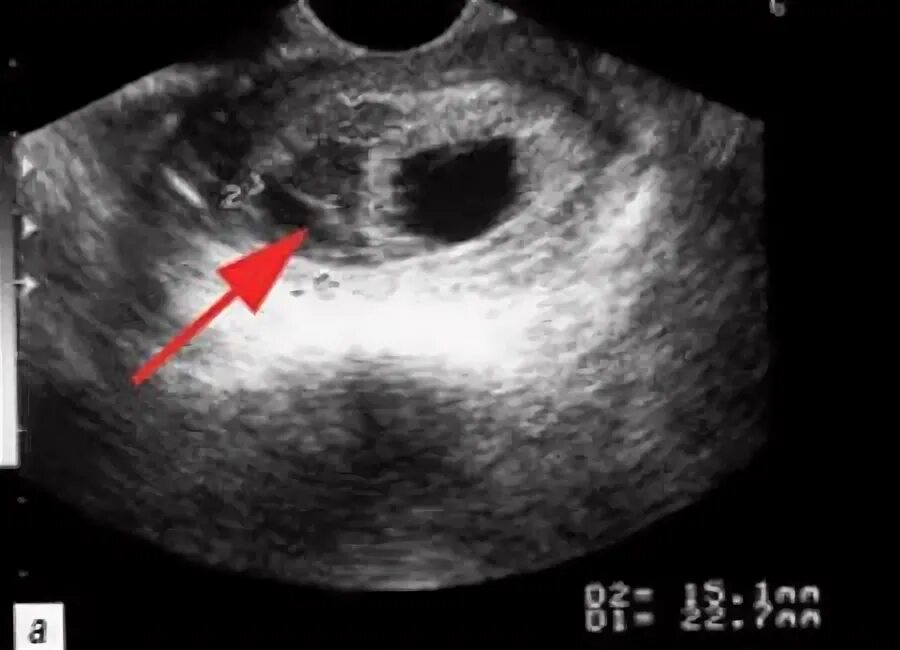

Как выходит гематома при беременности сроки